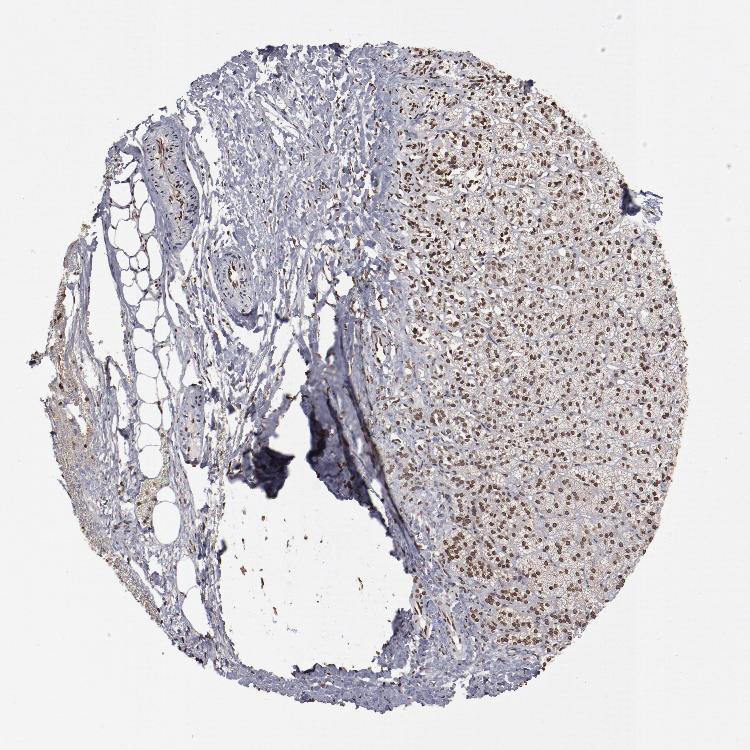

ADRENAL GLAND - Antibody stainingi

Antibody staining in the annotated cell types in the current human tissue is reported as not detected, low, medium, or high, based on conventional immunohistochemistry profiling in selected tissues. This score is based on the combination of the staining intensity and fraction of stained cells.

Each image is clickable and will lead to virtual microscopy that enables deeper exploration of all samples and also displays staining intensity scores, fraction scores and subcellular localization as well as patient and tissue information for each sample.

Antibody HPA002891Antibody CAB003765Antibody CAB080436

Glandular cells HighHighHigh